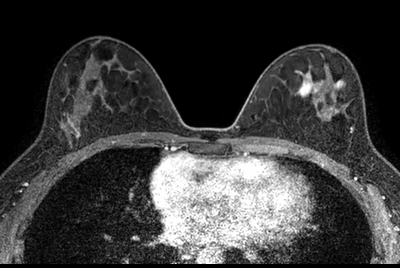

Breast biopsy with dS Sentinelle Breast coil

Dynamic Breast imaging with SmartSpeed AI

Breast 3D and 4D imaging